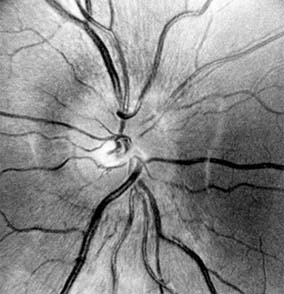

Figure 14-16

Figure 14-16: Atrophic papilledema in a child with a cerebellar medulloblastoma. The disk is pale and slightly elevated and has blurred margins. The white areas surrounding the macula are reflected light from the vitreoretinal interface. The inferior temporal nerve fiber bundles are partially atrophic (arrows).